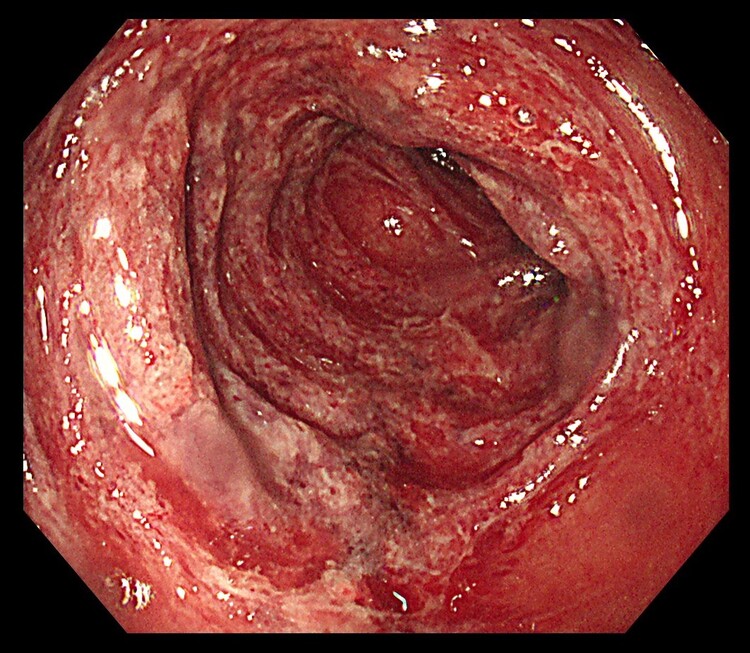

クローン病

クローン病は口から肛門までの、消化管全体に炎症が発生する原因不明の慢性疾患で、潰瘍性大腸炎と同様に国から難病に指定されています。

発症のピークは潰瘍性大腸炎よりやや若い10歳代〜20歳代の若年者で、男性に多く見られます。炎症の中心は、小腸や大腸で、下痢、血便・下血のほか、腹痛、体重減少、発熱などを伴います。

治療は薬物療法や栄養療法が中心で、重症例では外科手術が必要になることもあります。